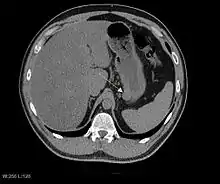

Imaging

The purpose of radiologic imaging is to locate the lesion, evaluate for signs of invasion and detect metastasis. Features of GIST vary depending on tumor size and organ of origin. The diameter can range from a few millimeters to more than 30 cm. Larger tumors usually cause symptoms in contrast to those found incidentally which tend to be smaller and have better prognosis.[4][13] Large tumors tend to exhibit malignant behavior but small GISTs may also demonstrate clinically aggressive behavior.[14]

Barium fluoroscopic examinations and CT are commonly used to evaluate the patient with abdominal complaints. Barium swallow images show abnormalities in 80% of GIST cases.[14] However, some GISTs may be located entirely outside the lumen of the bowel and will not be appreciated with a barium swallow. Even in cases when the barium swallow is abnormal, an MRI or CT scan must follow since it is impossible to evaluate abdominal cavities and other abdominal organs with a barium swallow alone. In a CT scan, abnormalities may be seen in 87% of patients and it should be made with both oral and intravenous contrast.[14] Among imaging studies, MRI has the best tissue contrast, which aids in the identification of masses within the GI tract (intramural masses). Intravenous contrast material is needed to evaluate lesion vascularity.

Preferred imaging modalities in the evaluation of GISTs are CT and MRI,[16]: 20–21 and, in selected situations, endoscopic ultrasound. CT advantages include its ability to demonstrate evidence of nearby organ invasion, ascites, and metastases. The ability of MRI to produce images in multiple planes is helpful in determining the bowel as the organ of origin (which is difficult when the tumor is very large), facilitating diagnosis.

Large GISTs

As the tumor grows it may project outside the bowel (exophytic growth) and/or inside the bowel (intraluminal growth), but they most commonly grow exophytically such that the bulk of the tumor projects into the abdominal cavity. If the tumor outstrips its blood supply, it can necrose internally, creating a central fluid-filled cavity with bleeding and cavitations that can eventually ulcerate and communicate into the lumen of the bowel. In that case, barium swallow may show an air, air-fluid levels or oral contrast media accumulation within these areas.[14][17] Mucosal ulcerations may also be present. In contrast enhanced CT images, large GISTs appear as heterogeneous masses due to areas of living tumor cells surrounding bleeding, necrosis or cysts, which is radiographically seen as a peripheral enhancement pattern with a low attenuation center.[13] In MRI studies, the degree of necrosis and bleeding affects the signal intensity pattern. Areas of bleeding within the tumor will vary its signal intensity depending on how long ago the bleeding occurred. The solid portions of the tumor are typically low signal intensity on T1-weighted images, are high signal intensity on T2-weighted images and enhance after administration of gadolinium. Signal-intensity voids are present if there is gas within areas of necrotic tumor.[15][18][19]

Features of malignancy

Malignancy is characterized by local invasion and metastases, usually to the liver, omentum and peritoneum. However, cases of metastases to bone, pleura, lungs and retroperitoneum have been seen. In distinction to gastric adenocarcinoma or gastric/small bowel lymphoma, malignant lymphadenopathy (swollen lymph nodes) is uncommon (<10%) and thus imaging usually shows absence of lymph node enlargement.[13] If metastases are not present, other radiologic features suggesting malignancy include: size (>5 cm), heterogeneous enhancement after contrast administration and ulcerations.[4][13][20] Also, overtly malignant behavior (in distinction to malignant potential of lesser degree) is less commonly seen in gastric tumors, with a ratio of behaviorally benign to overtly malignant of 3-5:1.[4] Even if radiographic malignant features are present, these findings may also represent other tumors and definitive diagnosis must be made immunochemically.